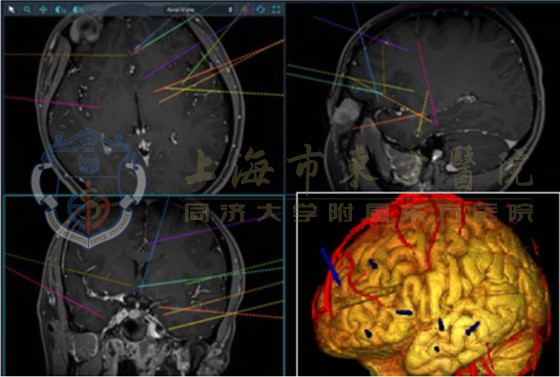

考虑做癫痫手术前必须先作一系列的检查,确定癫痫病灶区。首先必须先做影像检查,譬如MRI或CT,以便了解脑内是不是有肿瘤或病变;接着作一般性脑波检查及24小时脑波录像监测检查,了解癫痫发作的形态,并深查癫痫发作病灶在哪里;必要时必须在脑内植入硬脑膜下电极片或脑深部电极,直接记录到脑里面癫痫波的情形,进而更精确地定位出癫痫病灶,以便作切除手术。此外核子医学检查,譬如 SPECT或 PET,还有脑磁图(MEG)以及神经心理测验也可以作为辅助检查,找出病灶区。

3、SEEG立体脑电图引导下的射频热凝术,利用计算机辅助技术和CT、MRI、DTI图像融合技术进行术前定位,自动计算可疑脑内神经核团靶点即癫痫灶,然后将SEEG立体脑电图送至脑内靶点位置,进行脑深部局部脑电图监控,发现癫痫病灶后,进行可控性射频热凝调控。该技术定位精准,具有侵袭性小、副作用少且症状控制理想等优点,术后伤口愈合快、创伤面积小,大大降低了手术并发症的出现。